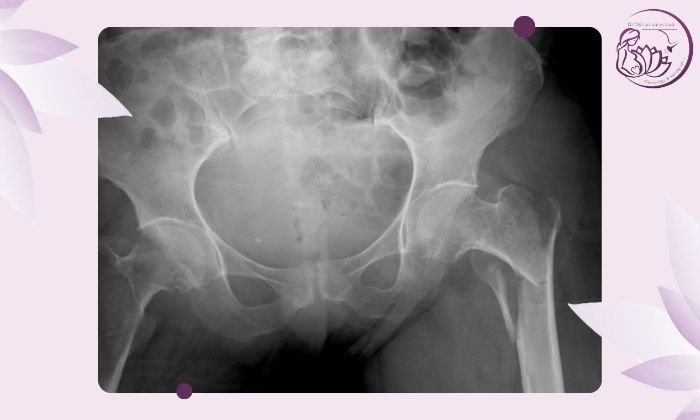

در صورت وجود هرگونه شی فلزی در محل عکسبرداری تصویر دچار سایه و اختلال میشود.

پر بودن مثانه میتواند ساختارهای درون لگن را جابهجا کرده و باعث کاهش وضوح عکس شود.توصیه میشود درست قبل از انجام عکسبرداری مثانه خود را کاملاً خالی کنید.